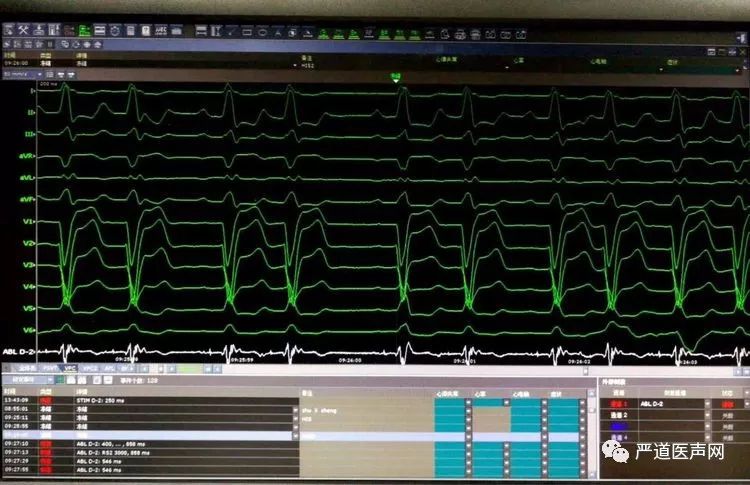

左束支起搏大致操作过程: 1.记录到希氏束电位:2.起搏观察希氏束起搏电图,看是否能够纠正LBBB。从图二可以看出,该患者希氏束稍虽然能改善LBBB,但QRS仍然较宽:3.记录到右束支电位:4.高电压起搏右束支,观察是否出现LBBB消失,QRS变窄:5.将主动电极旋转使其穿过室间隔,到达左束支区域,并记录到左束支电位:6.测试稍参数,观察LBBB消失及QRS变窄情况:7.植入心房电极,关闭囊袋。

希氏束电位

图二